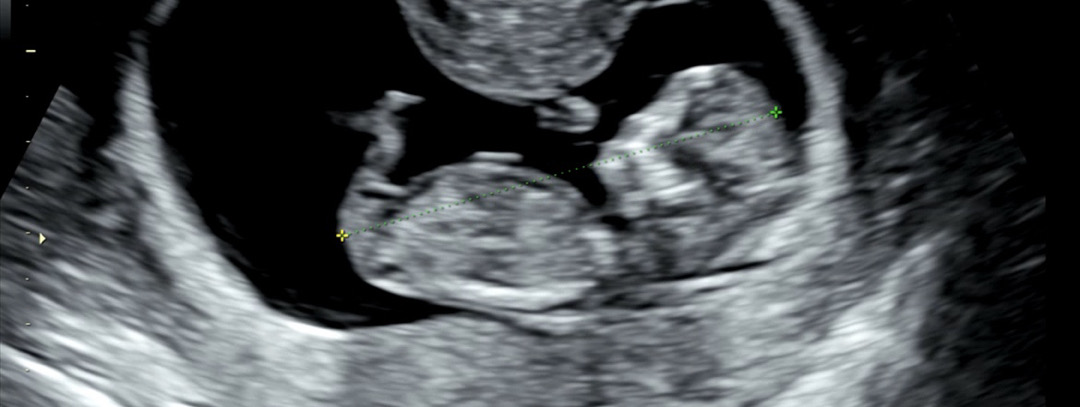

각도법 고수님들! 한번만 투표 부탁드려요!🥲

의사선생님 의견과 챗gpt와 각도법 의견이 달라요! 투표 한번만 부탁드려요! 감사합니다❤️